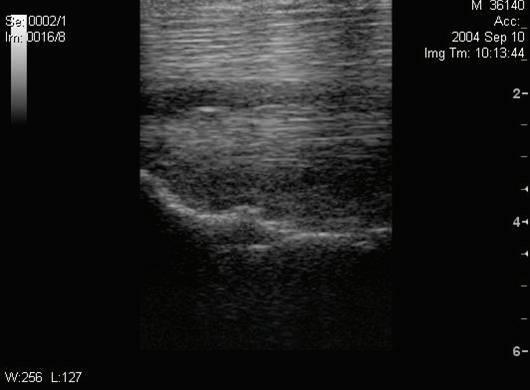

The soft tissue structures of the metacarpal and metatarsal regions are most commonly examined with ultrasound during purchase examinations. Previous palpation or thermography screening may have suggested soft tissue inflammation in a specific region that may be more completely evaluated with ultrasound.

There is a high incidence of suspensory ligament injury in jumper, dressage, and event horses.4 Similarly, injury to the flexor tendons and digital flexor tendon sheath (DFTS) is not infrequent with varying distribution of affected structures between the fore and hindlimbs.5 The tendinous and ligamentous structures of the pastern can also be injured and ultrasonographic assessment of this region should be included if physical examination fi ndings, such as swelling and sensitivity, sufficiently raise suspicion about these areas. The size, shape, and fiber pattern of the distal sesamoidean ligaments and flexor tendons should be compared between affected and non-affected limbs. The degree of DFTS eff usion and synovial proliferation as well as the thickness of the annular ligaments can also be evaluated.

Fig. 5: Left hind suspensory origin is thickened with an inhomogeneous fiber pattern. The origin enthesis is irregular compared to the right hind. The horse demonstrated a mild left hind lameness but no obvious enlargement on palpation.

Figure 5: Left hind suspensory origin is thickened with an inhomogeneous fiber pattern. The origin enthesis is irregular compared to the right hind. The horse demonstrated a mild left hind lameness but no obvious enlargement on palpation. Image courtesy of Dr. Richard D. Mitchell.